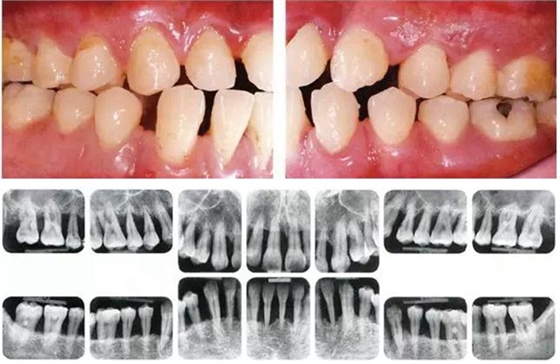

●49歲女性 慢性牙周炎(輕度)的口腔內(nèi)照片

49歲女性,接受過(guò)口腔衛(wèi)生士指導(dǎo),觀察發(fā)現(xiàn)頰舌側(cè)無(wú)菌斑,鄰接面有菌斑附著。牙周探診結(jié)果為全頜牙周袋深為3-4mm,同時(shí)拍攝口腔X片可觀察到全頜有輕度骨吸收。根據(jù)以上檢查、診查結(jié)果診斷出該患者為慢性牙周炎廣泛型(輕度)。視診觀察無(wú)牙齦腫脹、發(fā)紅等炎癥,觀察推斷可能是刷牙用力過(guò)度造成頰側(cè)牙齦萎縮。

●45歲女性 慢性牙周炎(重度)口腔內(nèi)照片

45歲女性,曾經(jīng)接受過(guò)口腔衛(wèi)生指導(dǎo)和牙周治療,菌斑控制情況除去部分磨牙部位其余基本良好。牙周探診檢查結(jié)果為全頜牙周袋深4~6mm,同時(shí)X片檢查數(shù)據(jù)可看到全頜重度骨吸收。根據(jù)以上檢查數(shù)據(jù)可診斷出該患者為慢性牙周炎廣泛型(重度)。牙齦沒(méi)有嚴(yán)重浮腫,但可觀察到紅褐色腫脹。上頜前牙有前突。